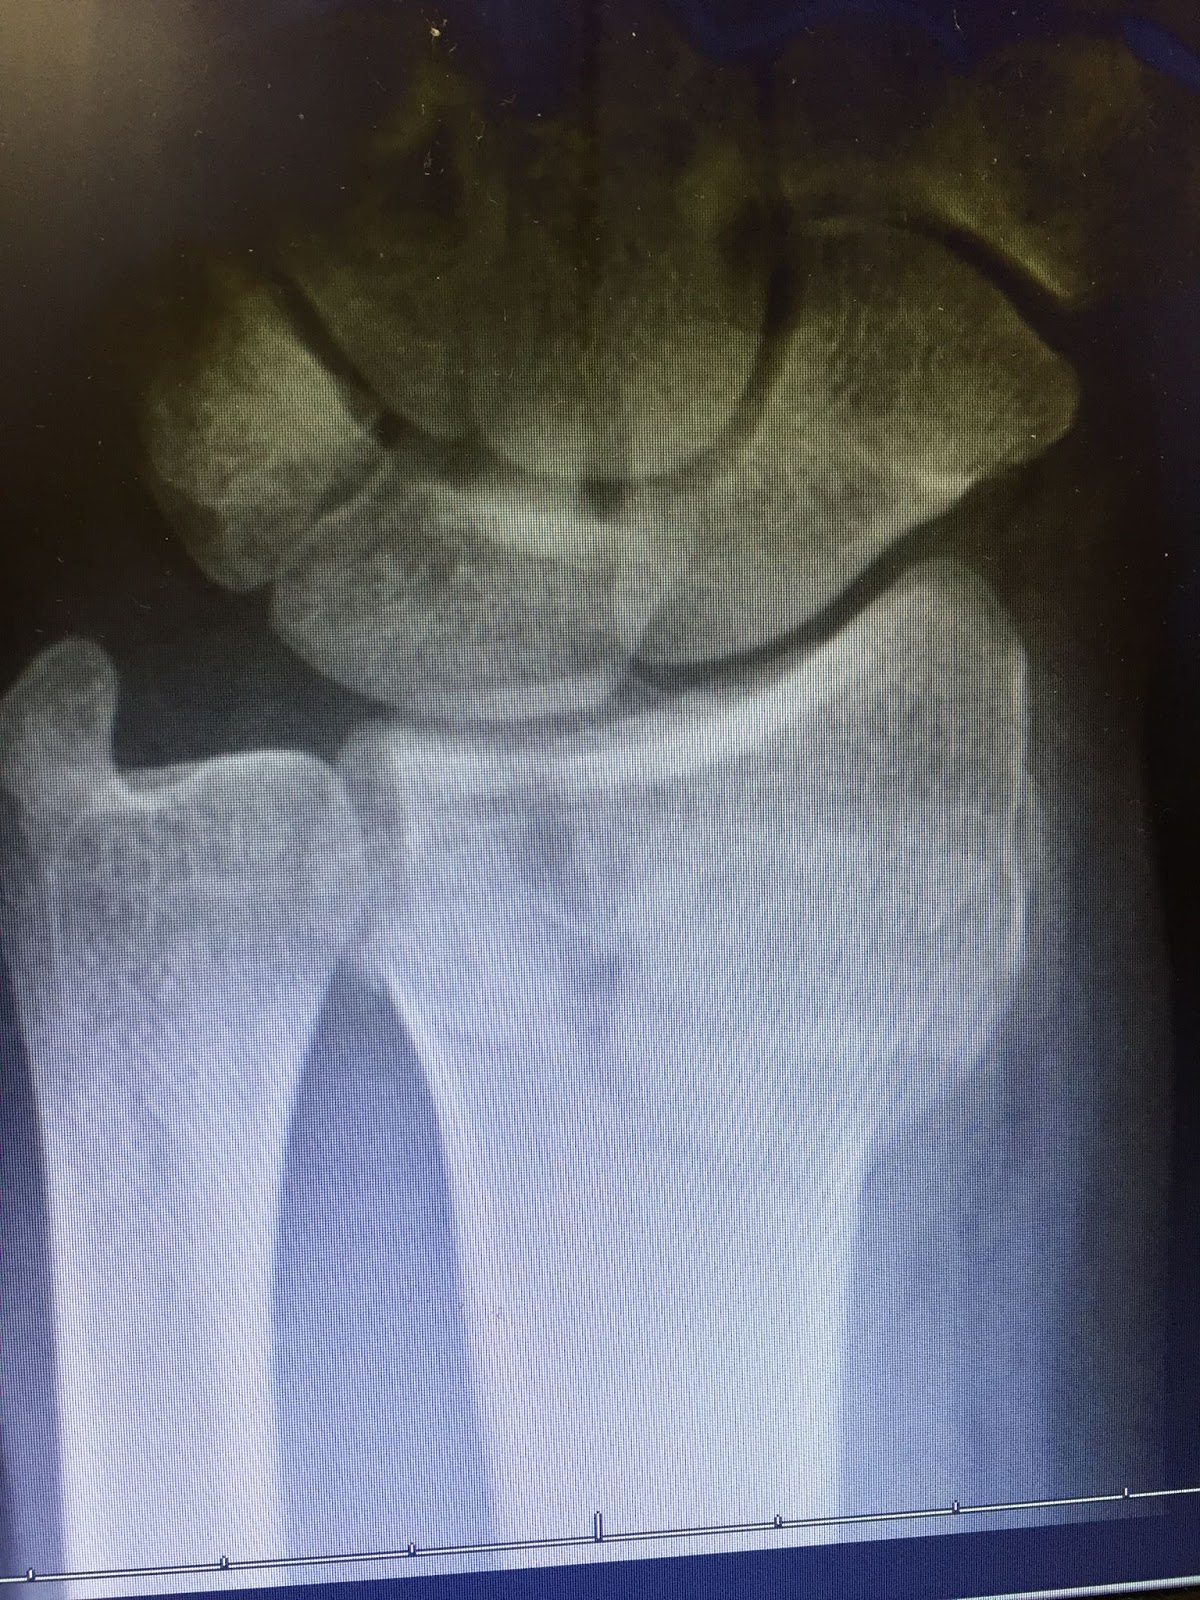

The attending physician looked at the x-rays and pronounced it broken—in a few pieces. He said I would likely need to have pins, screws, or plates installed. He gave me a prescription for a narcotic and sent me home.

The next morning I had an appointment with the orthopedic surgeon. He took more x-rays and said he thought he could put the bones in place and cast it, thus avoiding surgery. I readily agreed. He told me to clench my jaw, then he twisted and tugged a bit while I yelled in pain. But at least I didn’t have to go under the knife.